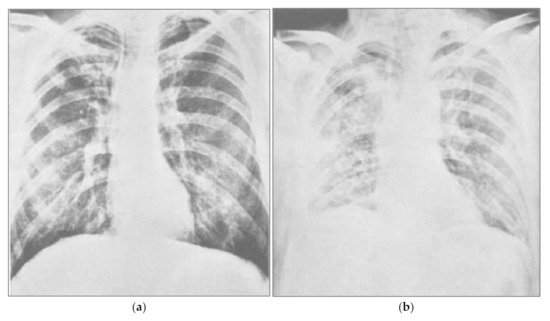

- Cozzi, D.; Cavigli, E.; Moroni, C.; Smorchkova, O.; Zantonelli, G.; Pradella, S.; Miele, V. Ground-glass opacity (GGO): A review of the differential diagnosis in the era of COVID-19. Jpn. J. Radiol. 2021, 1–12. [Google Scholar] [CrossRef]